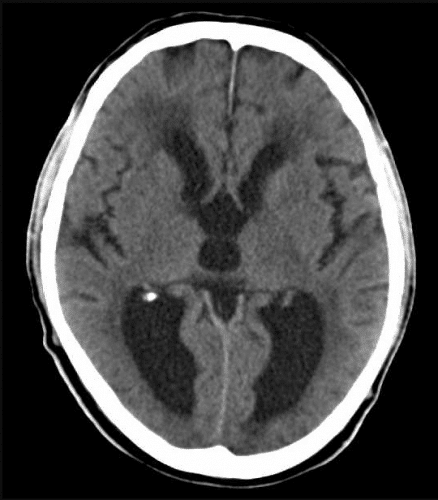

Hydrocephalus, CT scan – Stock Image – C018/0567 – Science Photo Library